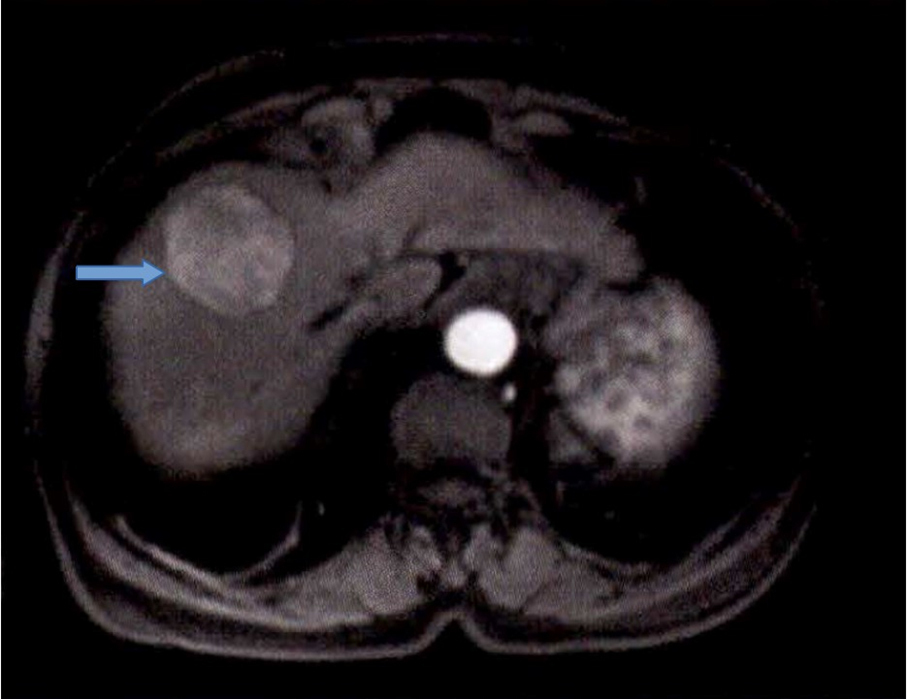

À l’examen clinique, vous retrouvez des signes d’insuffisance hépatocellulaire et d’hypertension portale associés à une hépatomégalie homogène à deux travers de doigts avec un bord inférieur tranchant. Le patient est marbré. Il existe une discrète ascite sans encéphalopathie associée. La palpation abdominale est indolore. Les constantes sont les suivantes : tension artérielle (TA) à 95/55 mmHg, pouls à 130/min, saturation en oxygène (SaO2) à 98 %, apyrétique.